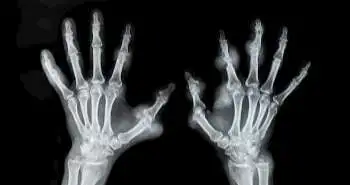

Sarcopenia is described by the muscle strength and mass loss, following falls and adverse health issues. The study intended to evaluate sarcopenia prevalence among rheumatoid arthritis (RA) patients and assess factors correlated with sarcopenia.

A  cross-sectional analysis with 388 consecutive RA women was conducted. The assessment of bone fractures and falls maintained above the previous year was done. Logistic regression analyses were used to assess sarcopenia association with RA characteristics, falls, and bone fractures.

The  37.1% prevalence was noticed for sarcopenia with 49.0% of low muscle mass. The RA patients with sarcopenia presented high rates of fractures, low bone mineral density and falls. The independent factors noticed to be related with sarcopenia were Steinbrocker’s stage, use of biological disease-modifying antirheumatic drugs (bDMARDs),  the high Mini-Nutritional Assessment-Short Form score, age, and RA duration.

Many patients with RA  known to develop sarcopenia. The bDMARDs showed negative, and other factors showed a positive relation with sarcopenia.